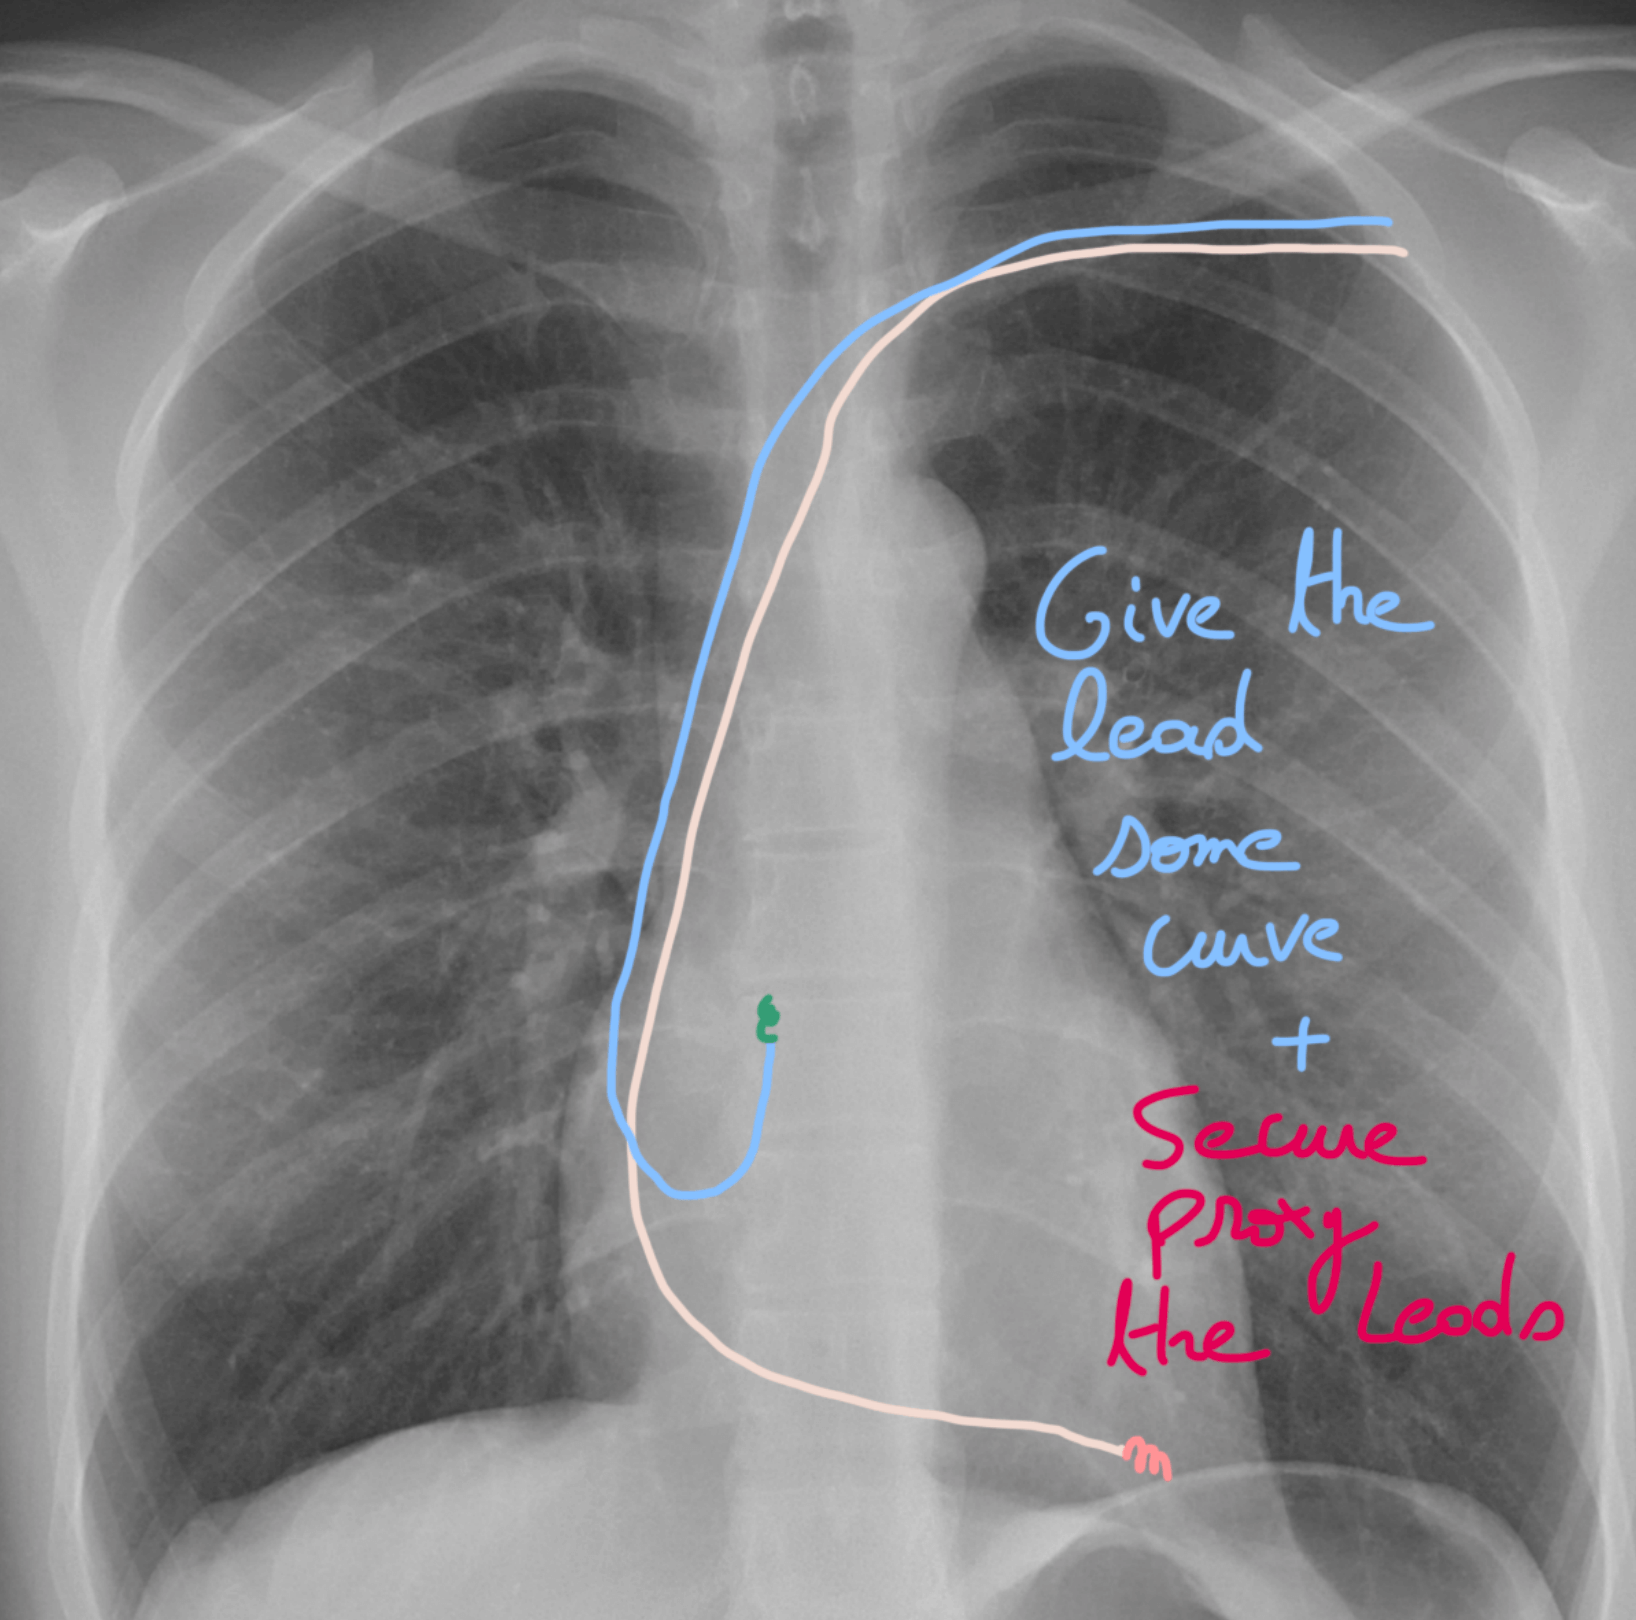

๐Ÿ”ฉ Step 19: Lock it in & test! ๐Ÿ“Š

If youโ€™re happy with the current of injury โœ…, you can now screw in your lead ๐Ÿช›.

๐Ÿ‘‰ Then check the key parameters:

Sensing ๐Ÿ‘‚โšก

Threshold ๐ŸŽฏ

Impedance ๐Ÿ“‰

If everything looks good ๐Ÿ‘, you can secure the lead proximally so it stays right where it belongs.

Think of it like anchoring your spaceship ๐Ÿš€ before take-off โ€” stable, safe, and ready to perform!